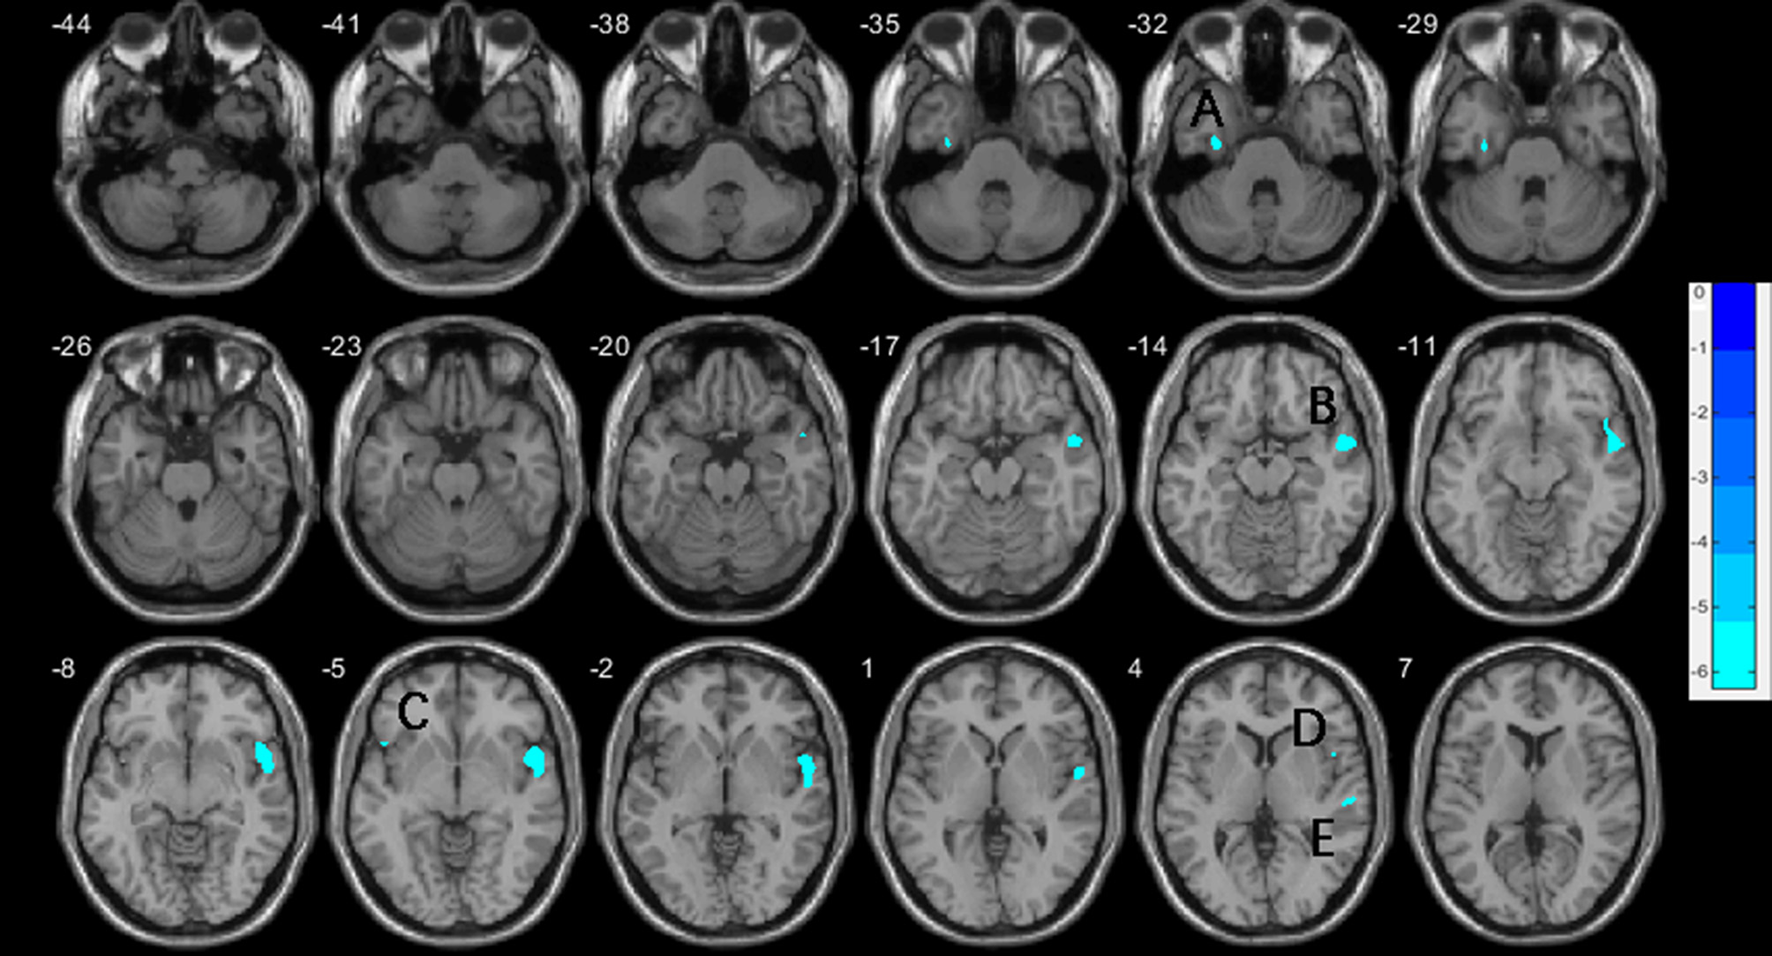

One-way ANCOVA (P < 0.001, uncorrected) revealed significant differences in GMV in widespread regions, including the right superior temporal gyrus (STG), right insula gyrus (INS), right temporal pole (superior and middle temporal gyrus [TP]), left fusiform gyrus (FFG), left parahippocampal gyrus (PHG), bilateral medial orbital frontal gyri (mOFG), bilateral orbital inferior frontal gyri (IFGorb) and left inferior parietal lobe (IPL), between the three groups. Post-hoc t-test showed that, compared to HCs, vSZ showed significantly reduced GMV in a large cluster from the right STG to the insula (INS), TP, and IFGorb. Other regions showing reduced GMV in the vSZ group were the left FFG, IFGorb, and right opercular IFG (IFGoper) (P < 0.05, FWE corrected; Table 2; Figures 1, 3). In the nvSZ group, reduced GMV was found in the left IPL, PHG, the bilateral mOFG, and the right superior TP and IFGorb, as compared to the HC group (P < 0.05, FWE corrected; Table 2; Figures 2, 3). Marked decrease was found in the GMV of the right temporal lobe and bilateral IFG in the vSZ group rather than the nvSZ group, as compared with HCs. In addition, a more pronounced decline of GMV in the left IPL was found in the nvSZ group as compared to the vSZ group, although there was no significant difference. The results obtained by using TFCE were quite similar with our original results (see Supplementary Table 1; Supplementary Figures 1–3).

Figure 1

Decreases of gray matter volume in the vSZ group compared to HCs, with age, education, and TIV controlled. (A) left fusiform gyrus; (B) right superior temporal gyrus; (C) left inferior frontal gyrus, orbital; (D) right inferior frontal gyrus, operculum; (E) right superior temporal gyrus. TIV, total intracranial volume.